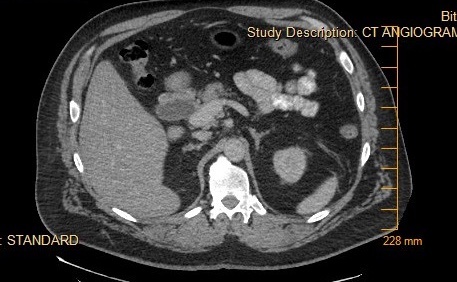

His laboratory values were significant for elevated total and direct bilirubin (22.4 and 15.9 mg/dl). Additional lab values include – an AST (137 U/L) and ALT (232 U/L), and an abnormally elevated Lipid panel with LDL (263 mg/dl), triglyceride (357 mg/dl), and total cholesterol (346 mg/dl). On day three of admission, the patient underwent an endoscopic retrograde cholangiopancreatography (ERCP) with findings significant for multiple gallstones in the common bile duct (Fig. 1 - 4) consistent with Mirizzi syndrome.

On the ERCP, patient had outpouching in the cystic duct. A stent was placed in the common bile duct (CBD). The patient’s direct bilirubin decreased from 7.4 mg/dl to 5.9 mg/dl. The patient was scheduled to follow up with gastroenterologist in two to three weeks for the removal of the CBD stent, and he improved markedly post-stent placement. He was asymptomatic on discharge.